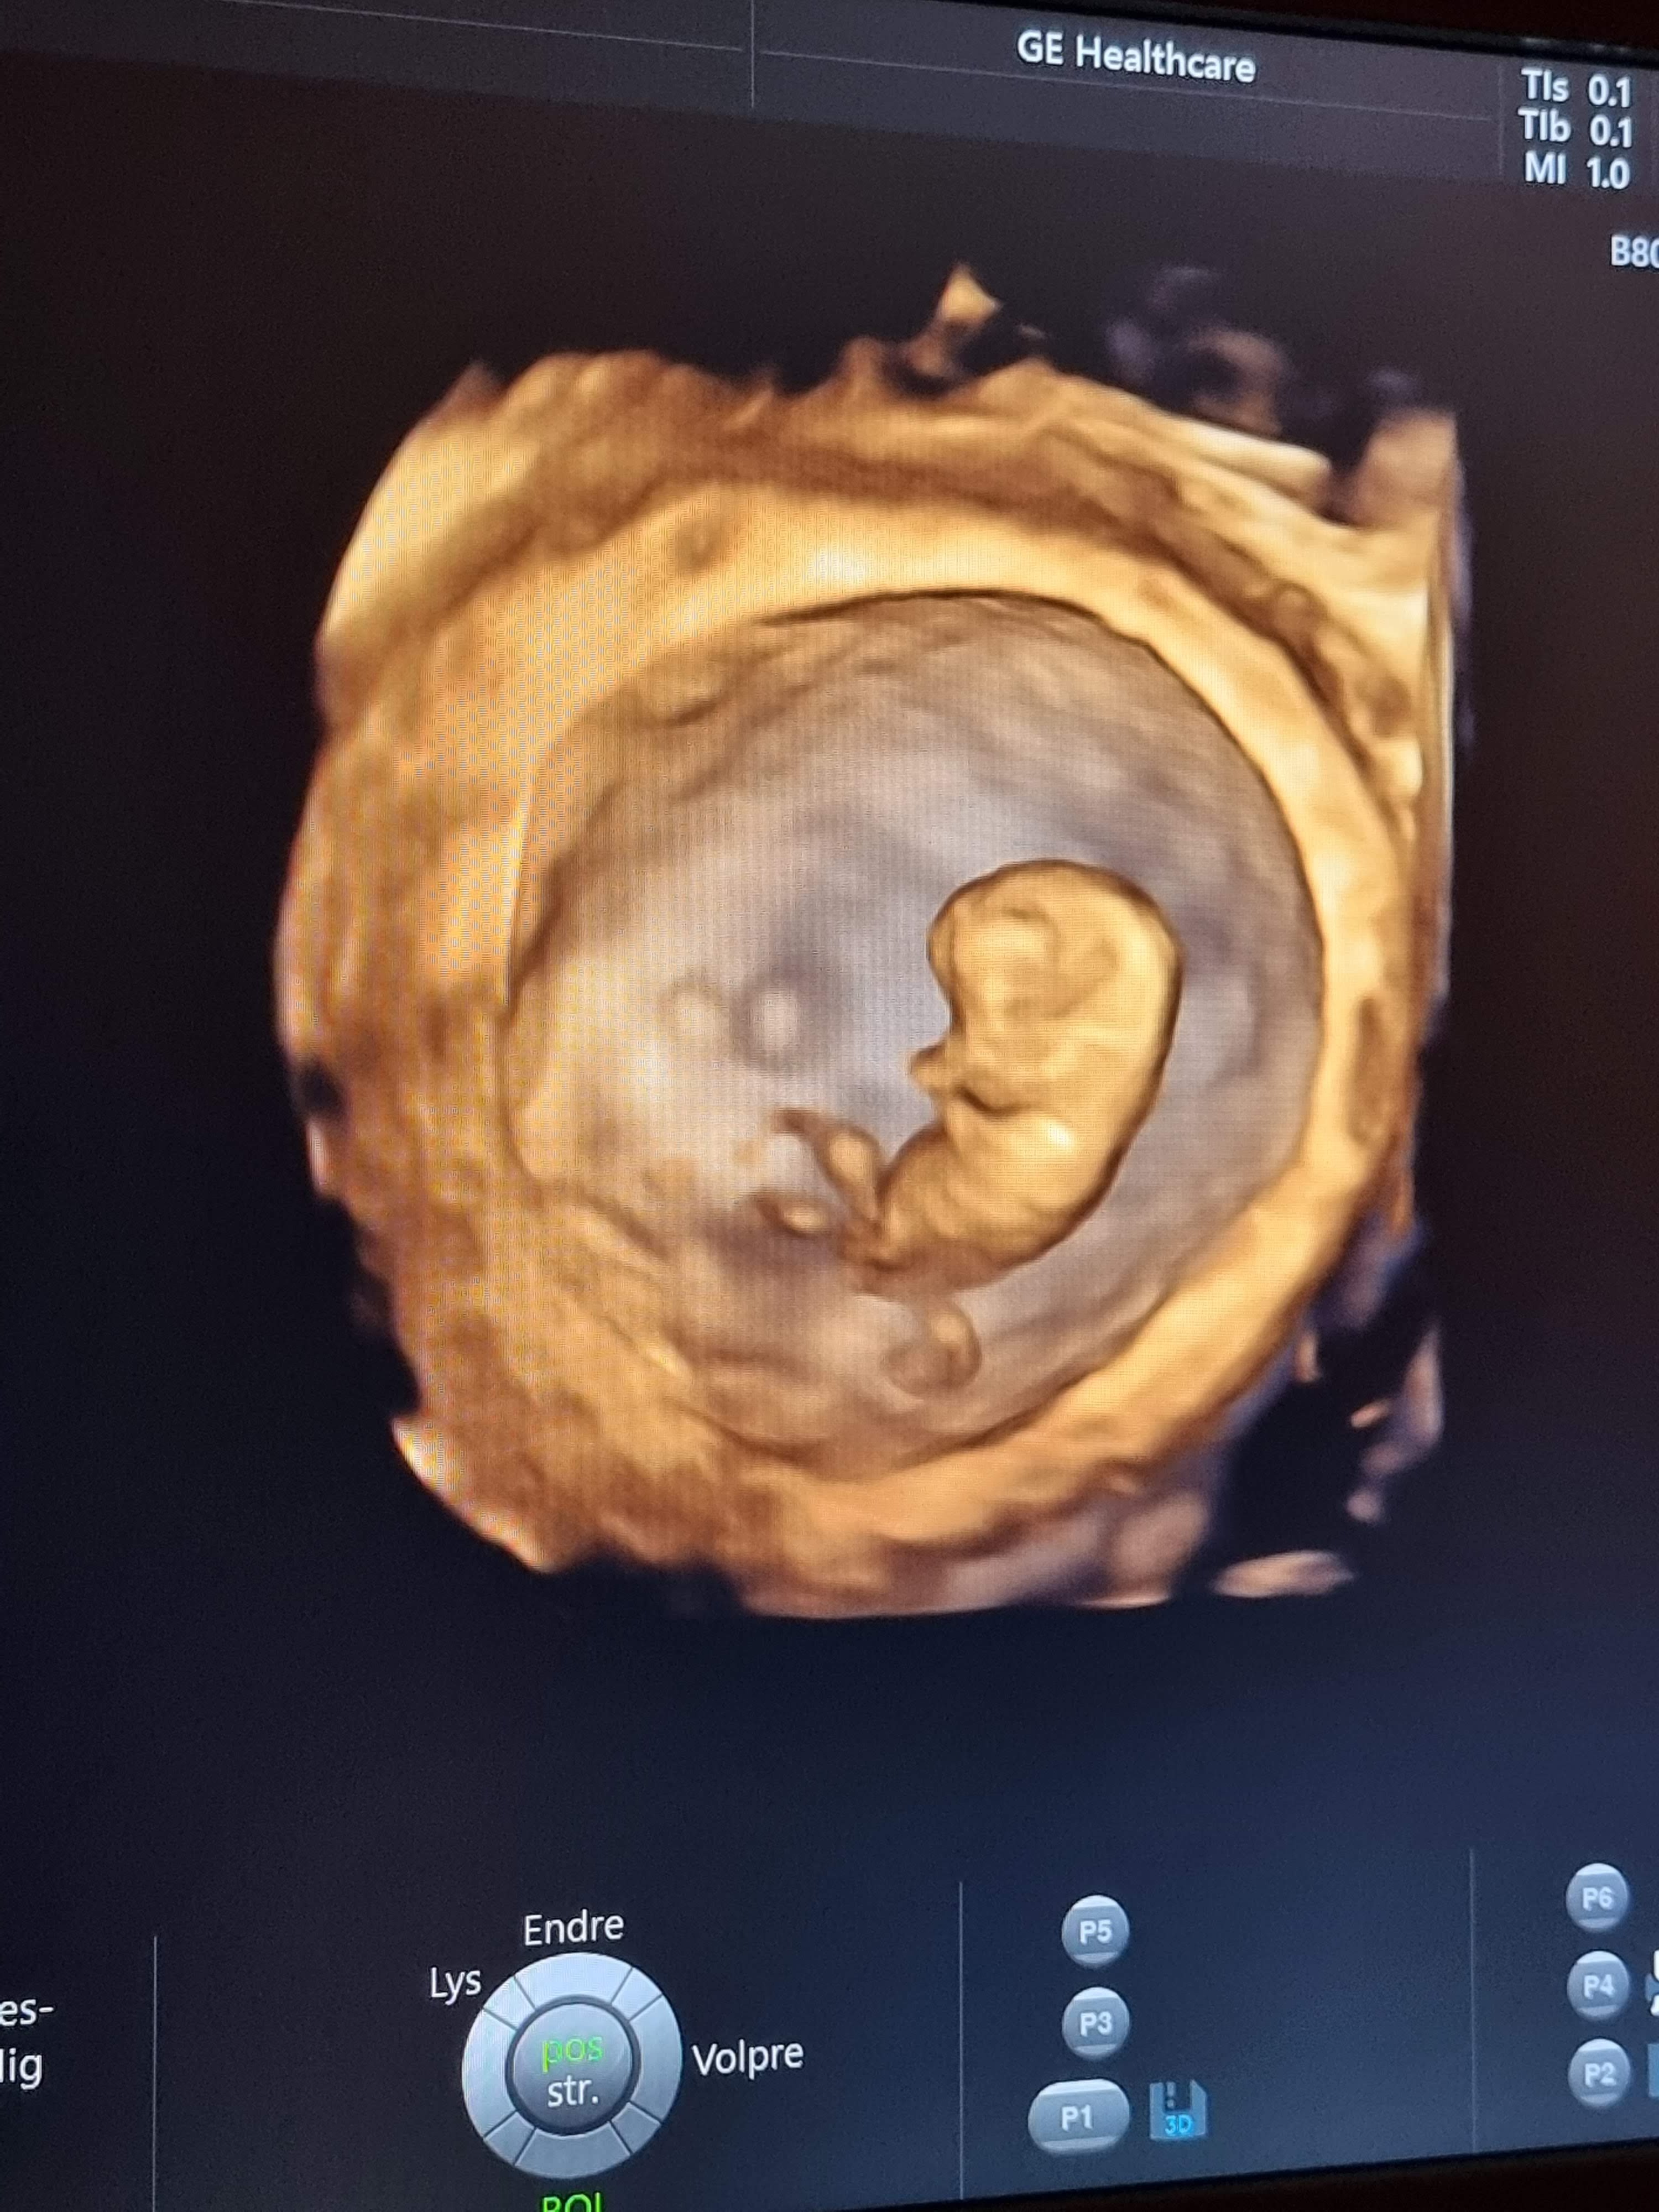

Men jeg var på ny ultralyd i dag, og alt er heldigvis fortsatt i skjønneste orden

Fikk også tatt en liten videosnutt hvor man ser fosteret bevege seg. Så utrolig stas å se!! Dette var egentlig siste gang hos offentlig gynekolog, men jeg spurte om det var siste timen, og han sa at jeg godt kunne få en til hvis det hjalp meg. Sa selvfølgelig ja til det!

Helt uvirkelig å se!!